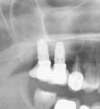

L’image radiologique post-opératoire montre les deux implants ancrés dans la poudre d’os qui a servi à combler le sinus maxillaire.

Cas 1: Le comblement sinusien maxillaire consiste à créer un volume osseux dans le sinus maxillaire pour y ancrer des implants.

Une poudre d’os est placée pour combler le sinus maxillaire et permettre la pose d’implants.